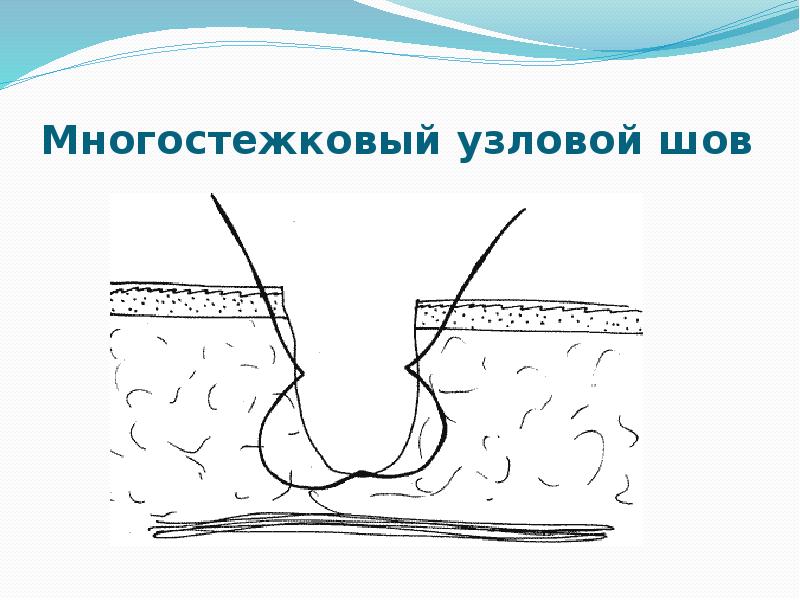

- 38. Многостежковый узловой шов